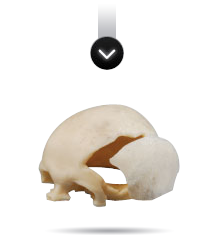

El prototipo plástico se consigue a partir de la realización de un modelado digital 3D. La pieza obtenida respeta las medidas de la anatomía, pudiendo el cirujano, de esta manera, tener una idea real de la patología a tratar.

Una vez obtenida la información de la TAC o MRI y modelado el 3D digital, podemos modelar la prótesis que se necesita (por ejemplo, una porción de calota faltante) y posteriormente realizarla en resina plástica. De esta manera validamos la adaptación del futuro implante a la anatomía. El cirujano puede verificar las imágenes modeladas digitalmente o el prototipo en resina plástica, y sugerir modificaciones dando paso al proceso final.

En otros casos el cirujano puede solicitar el modelado de alguna región anatómica con la finalidad de hacer una planificación prequirúrgica, por ejemplo, realizar en su consulta un moldeado muy exigente de placas maxilares. Luego de recibir el modelo anatómico o prototipo en resina, modela las placas que va a utilizar y las devuelve a la empresa para que sean esterilizadas antes de ser usadas, reduciendo considerablemente el tiempo quirúrgico.

Antes de la fabricación del implante, el cirujano puede elegir entre dos métodos de examen del implante PROTOLAB: 1) Un modelo del cráneo y del implante para ser examinado, marcado o aprobado;

Cuando ha establecido el diseño final del implante y se ha recibido una aprobación, PROTOLAB fabricará un implante no estéril para enviar al cirujano.